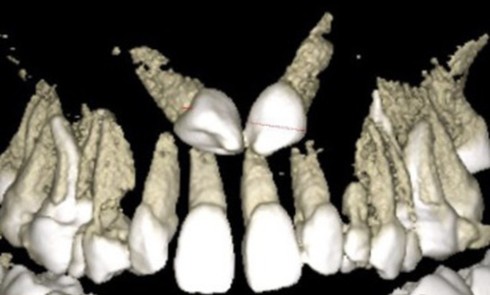

Présentation du cas (fig. 1 à 9) Madame J, âgée de 49 ans, nous est adressée par son occlusodontiste pour...